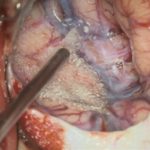

術中写真

摘出 中